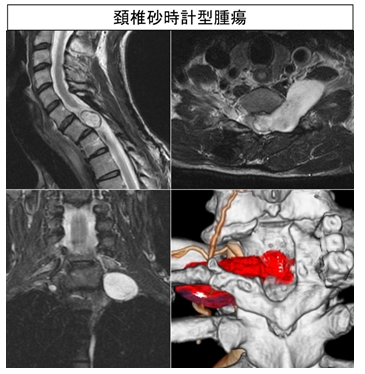

腫瘍性疾患

原発性脊椎腫瘍に対しては、悪性でも単発なものは脊椎全摘術を行います。転移性脊椎腫瘍に対しては、転移性骨腫瘍ボードなど関連各科と連携をとりながら、化学療法や放射線治療を併用した脊椎インストゥルメンテーションを用いた腫瘍摘出・除圧固定術を行っています。

脊髄腫瘍に対しては、顕微鏡下での腫瘍摘出術を行っています。